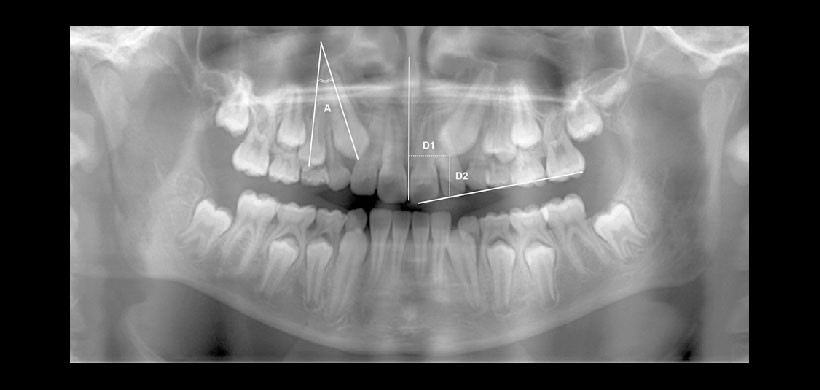

Fig 1. Manera correcta de trazar los ejes longitudinales de los dientes, nótese que va desde el eje radicular hacia el eje coronal de la línea media, Se observa la correcta visualización de los planos oclusa.es y de la línea medio sagital.

Fig 2. Manera de cómo realizar las mediciones angulares y lineales. Si la angulación del canino con el del primer premolar es mayor al valor normal, entonces hay mayor probabilidad de impactación; Si las distancias entre la cúspide del canino con la línea media sagital es menor o la distancia entre la cúspide y el plano de oclusión es mayor a los valores normales entonces existirá mayor predicibilidad de impactación.